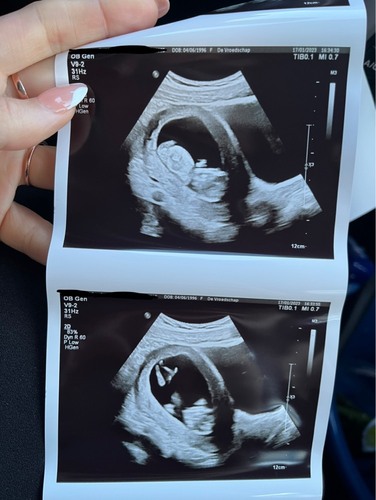

Vandaag dan (eindelijk) de 13 weken echo gehad met 14+3, we zijn ongeveer een half uur bezig geweest om alles te meten omdat de kleine frummel niet stil wilde liggen en telkens met de rug naar ons toe ging liggen. De basis ziet er perfect uit 🥰